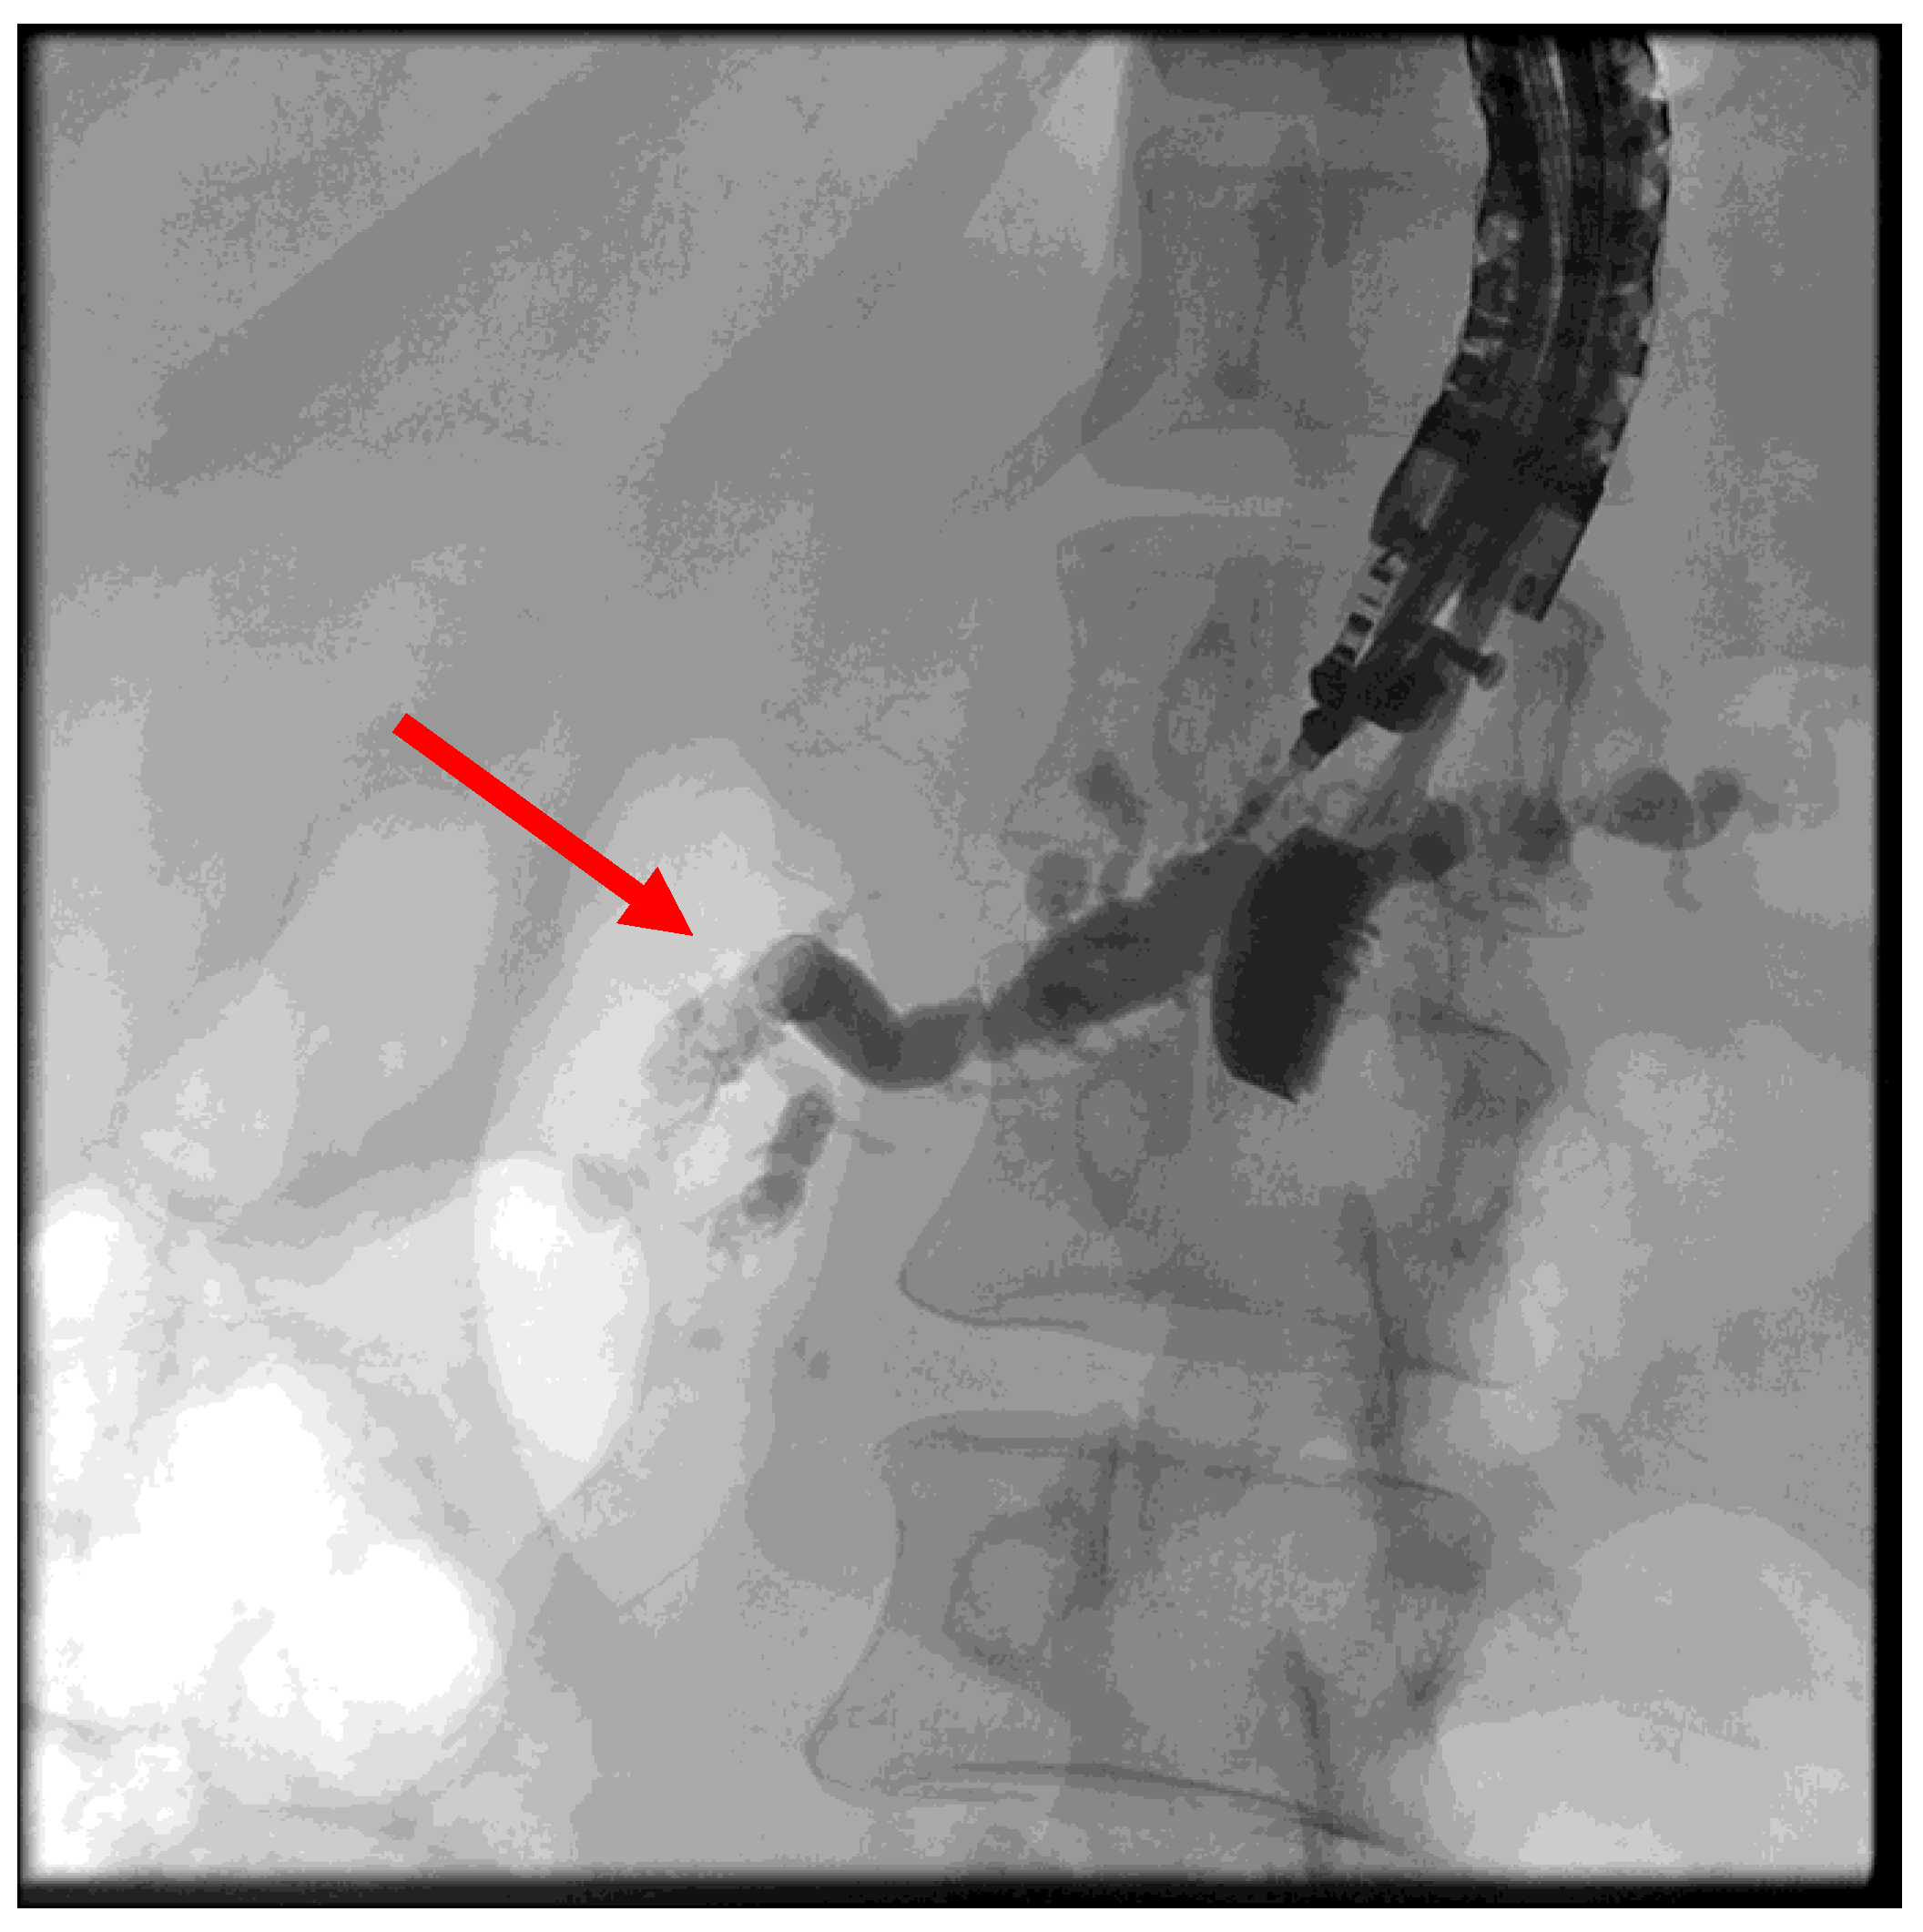

The patient is positioned prone on an X-ray fluoroscopy table and undergoes endoscopic ultrasound (EUS) using a therapeutic longitudinal scanner (e.g., EG 3270 UK, Hitachi Ultraschall, Berlin, Germany; GF-UCT 180, Olympus, Hamburg, Germany; Fuji EG-580UT2, Tokyo, Japan) following unsuccessful conventional ERP, with peri-interventional antibiotic administration i. v. (2 g ceftriaxone or 4 g tazobactam). Once the pancreatic duct is identified, a 19-G needle (Boston Scientific, Ratingen, Germany; Olympus, Hamburg, Germany) is used to puncture it in the direction of the anastomosis or papilla. Pancreatic juice is aspirated and sent for microbiological and cytological examination. Subsequently, the pancreatic duct is visualized via X-ray fluoroscopy following the instillation of the contrast medium (Figure 1 and Figure 2—selected from the clinical picture library of the reporting Dept. of Gastroenterology, Hepatology and General Internal Medicine as all the following figures).

Figure 2. Intraprocedural fluoroscopy (during EUS-guided procedure): Legend see also Figure 1.